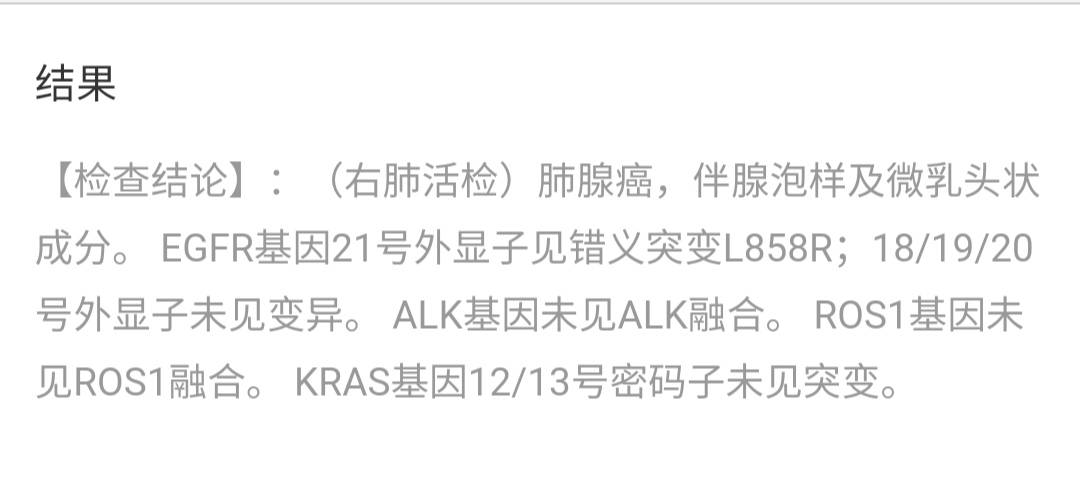

妈妈的基因检测出来了,egfr21突变'L858r 查了一些资料,越看越焦虑,想给妈妈最优的选择,但似乎没有绝对哪种靶向药最适合我们。